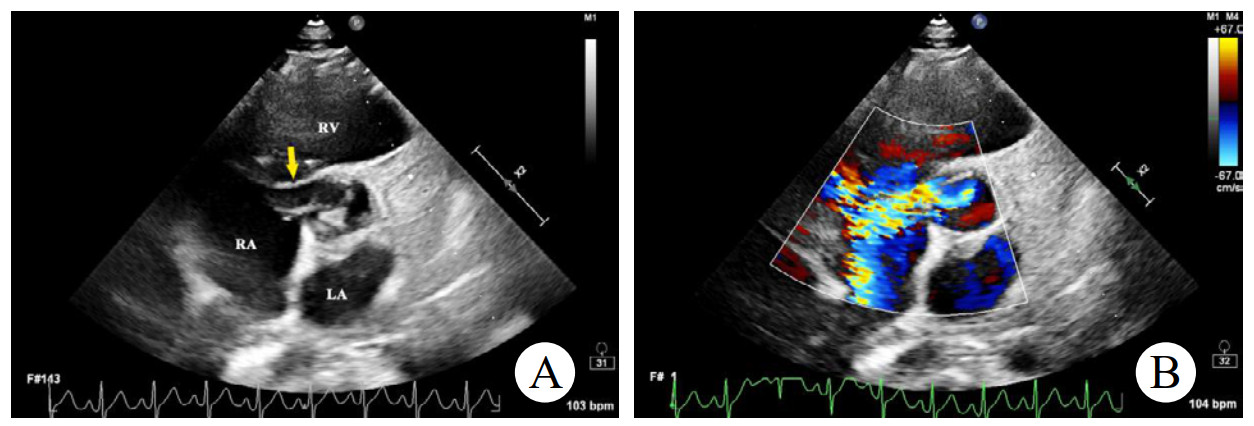

辅助检查如下。实验室检查:高敏C反应蛋白(hs-CRP)和红细胞沉降率(erythrocyte sedimentation rate, ESR)轻度升高。心电图:正常窦性心律,无ST段异常改变。胸部CT:双侧肺门中心对称分布的斑片状高密度影,部分实变,伴空气支气管征,病变边缘模糊。超声心动图:二维超声(2D)主动脉短轴切面显示右乏氏窦瘤破裂(ruptured of ASV, RASV),破入右心房形成“囊袋状”结构,长约1.7 cm,基底部破口内径约0.8 cm(图 1A)。彩色多普勒(color Doppler flow imaging, CDFI)显示全心动周期的左向右分流(图 1B)。连续多普勒(continuous doppler, CW)测得连续分流。室间隔内见4.0 cm×0.7 cm无回声区(图 2A),CDFI显示彩色血流信号随心动周期进出该无回声区(图 2B),考虑室间隔夹层瘤(dissecting aneurysm of the interventricular septum, DAIS)。实时双平面成像同步显示窦瘤破口与室间隔夹层相延续。应用Philips TrueVue三维(three-dimensional, 3D)超声心动图成像模式直观展示室间隔夹层瘤的立体结构(图 3)。

| 注:A为2D超声显示室间隔内无回声区(黄色箭头);B为CDFI显示彩色血流信号进出室间隔无回声区 图 2 2D及CDFI显示左室短轴二尖瓣水平切面室间隔夹层动脉瘤 |